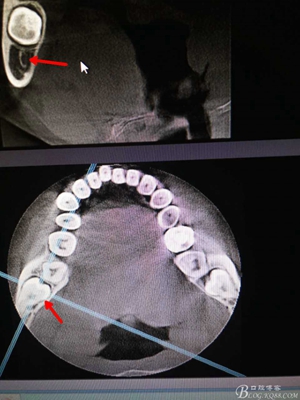

圖2.術(shù)前的cbct檢查:38牙冠周圍有骨組織覆蓋,下頜神經(jīng)管離38牙冠還有一定距離,在去除牙冠的時候,損傷神經(jīng) 的風險較小。38牙根舌側(cè)骨壁較薄。

圖3.冠向檢查:38牙根未進入下頜管內(nèi),牙冠周圍有牙囊影。